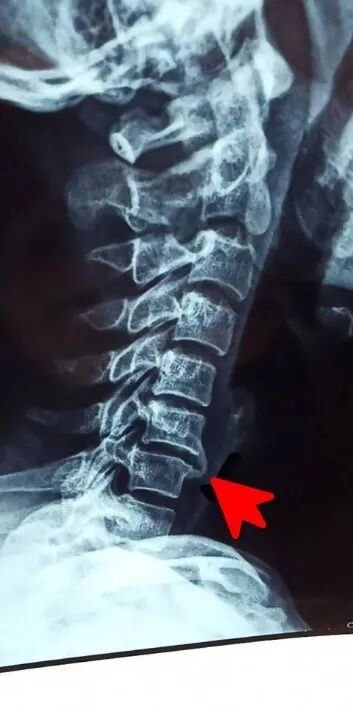

颈椎长“骨刺”往往和颈椎长期承受慢性劳损有关系。比如长期保持同一个姿势,低头工作、低头看手机,颈椎每天承受“重压”,就更容易使椎间盘、椎骨、韧带等结构会逐渐发生退化,从而导致颈椎稳定度降低。作为长期刺激、损伤的后果,以及颈椎为了维持脊柱稳定的代偿机制,颈椎椎骨周缘就会长出新的骨质,也就是通常所说的骨刺。骨刺是机体的一种防御机制,是来保护受损的颈椎,保护关节,防止产生进一步的损害。

颈椎过度活动在椎体前方产生的骨刺有助于稳定颈椎

但是骨刺的好坏随着骨刺生长的部位、大小、性状的不同而不同,当形成的骨刺生长到神经或血管旁,即便不大也可能对神经、血管造成压迫和损伤,表现出相应的症状体征,就会引发颈椎病。极少数的情况下,甚至会有巨大的骨赘压迫食管,造成吞咽困难。

生长在神经边上的“坏”骨刺

骨刺本是机体应对慢性损伤的一种代偿机制,意在维持颈椎结构的稳定,但当骨刺“越界”就会损伤神经和血管,“好”骨刺就变成“坏”骨刺,成为颈椎病的病因之一。